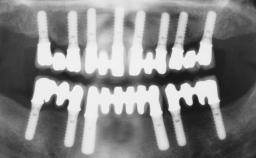

Immediate Loading of Four Implants in the Mandible and Six Implants in the Maxilla and Final Restoration with a Full-Arch Metal Framework FDP and a Full-Arch CAD/CAM Zirconia Framework FDP

A 65-year-old female patient with a failing residual maxillary dentition and a complete mandibular removable denture was referred for consultation and treatment. The patient’s chief complaint was that her upper residual teeth were mobile and she was unable to chew. The patient also asked us to improve the esthetic appearance of her smile. The patient’s desire was a stable and comfortable dentition in both jaws, and she specifically asked for a fixed rehabilitation. The patient reported a history of recurrent caries, endodontic complications, and periodontal disease as main reasons for previous teeth extractions. The anamnesis was negative for bruxism and TMJ disorders. The patient had no systemic diseases, was not on any medication,and did not smoke. The extraoral examination revealed a medium lip line, a wide diastema between the two central incisors (which, according to the patient, had appeared recently), and a partial collapse of the perioral soft tissues, probably due to loss of the correct vertical dimensions.

# of Implants 10

Type of Implants Two-Piece

Loading Protocol Immediate